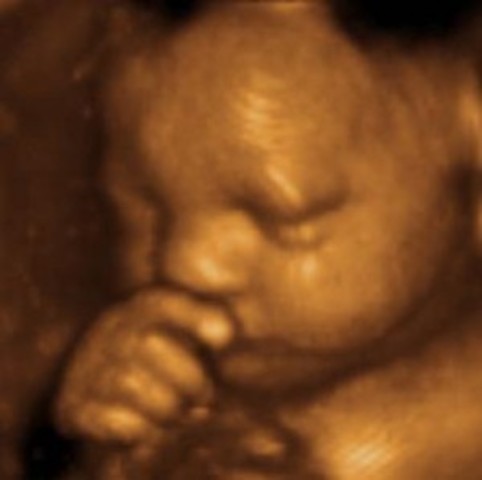

• Development of 3-D

Development of 3-D

3-D ultrasound was developed and 3-D images were captured of a fetus. A 3D ultrasound is acquired by emitting high-frequency sound waves. Researchers in Scotland began working on a multiplanar scanner. As computers developed, a true 3D ultrasound became more feasible. In 1984, the first concrete work on a Japanese 3D ultrasound began, and was successful by 1986. -WiseGeek Reference:

• Development of 4-D (Real Time) / Ultrasound Progression

Development of 4-D (Real Time) / Ultrasound Progression

4-D ultrasound (real time) was developed . Ultrasound guided biopsies were also beginning to develop into everyday practice. Due to the fact that 4D machines create a higher quality image, there is some concern that the energy level used by them may be higher, although this has not been proven. -WG Reference: